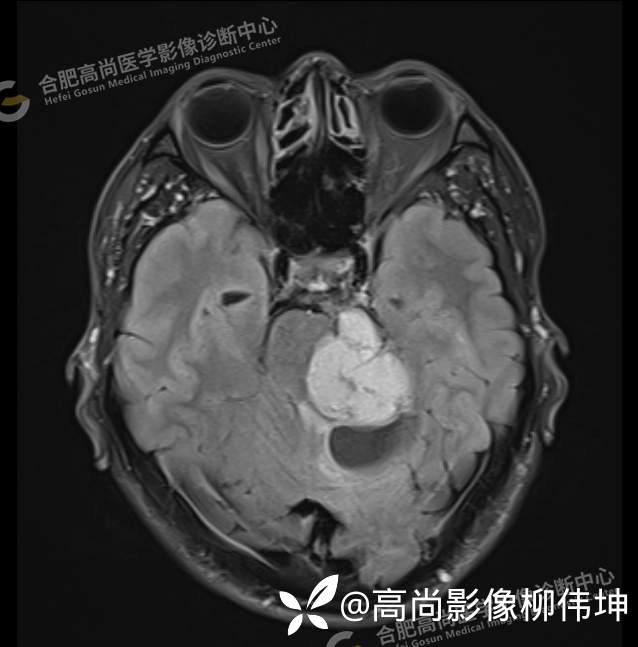

T2WI-tra

颅脑MRI平扫+增强示:双侧大脑半球对称,左侧桥小脑角区可见一团块状异常信号影,边界尚清,病灶与小脑幕宽基底附着呈“D”字征,上缘指状伸入幕缘上生长,病灶大小约43mmx42mmx36mm,其内信号不均,T1WI呈等低信号,T2WI呈混杂等高信号;FLAIR呈高信号,内可见条状低信号影,DWI呈稍高信号,ADC呈低信号,弥散轻度受限,病灶后方左侧小脑半球区可见一大小约33mmx16mm的弧形长T1长T2信号影,FLAIR呈低信号,其周围可见片状高信号影,相邻桥小脑角增宽。脑桥、小脑蚓部,小脑半球、第四脑室、环池受压变形,向右侧偏移,四脑室明显变窄,增强扫描病灶可见不均匀明显强化,邻近脑膜可见线样强化改变。其后方囊性灶未见异常强化。邻近骨质未见明显异常信号。左侧内听道显示正常;左侧中耳乳突内可见不规则性长T1长T2信号影。余脑实质内未见局灶性信号异常。双侧侧脑室及第三脑室体积增大,中线结构居中。矢状面示垂体形态大小正常,未见局灶性异常信号。

1.左侧桥小脑角区占位伴周围囊变,轻度梗阻性脑积水;考虑左小脑幕脑膜瘤。